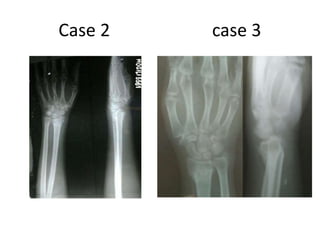

Case 2 case 3